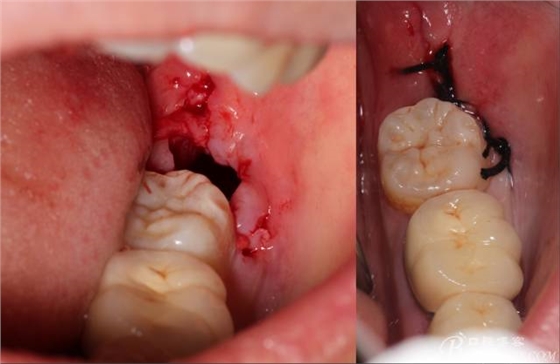

計(jì)劃總趕不上變化,何況是充滿變異的智齒。由于可操作空間較小,原來計(jì)劃?rùn)M向分根改成矢狀分根。

640 (15).jpg

現(xiàn)在都在提倡微創(chuàng),個(gè)人看法微創(chuàng)是相對(duì),所當(dāng)然微創(chuàng)是我們的追求。完全撥出,縫合關(guān)閉創(chuàng)口,常規(guī)智齒撥除醫(yī)囑,不適隨診。

640 (16).jpg

640 (17).jpg